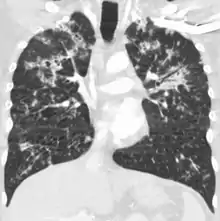

X-ray, 13 days after onset, showing bilateral interstitial infiltrates